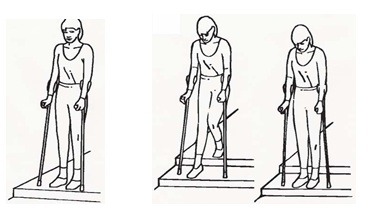

نکاتی در مورد بالا و پایین رفتن از پلهها: پلکان بدون نرده

به کمک چوبهای زیر بغلی که نزدیک به پلهها نگه داشتهاید بایستید و از پلهها بالا بروید. اول پای سالم را روی پله بالایی بگذارید، سپس پای عمل شده را بلند کنید. در انتها چوبهای زیر بغل را روی پلهها بگذارید.

برای پایین آمدن از پلهها ابتدا چوبهای زیر بغل را روی پله پایینتر بگذارید، سپس پای عمل شده و در نهایت پای سالم را روی همان پله پایینی بگذارید.

برای پایین آمدن از پلهها ابتدا چوبهای زیر بغل را روی پله پایینتر بگذارید، سپس پای عمل شده و در نهایت پای سالم را روی همان پله پایینی بگذارید.